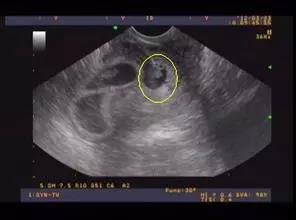

怀孕期间,孕妇们会经历多次B超检查,以确保胎儿的健康发育。其中,25周的系统B超检查尤为重要,它不仅能够全面了解胎儿的生长发育情况,还能对孕妇的养生保健提供指导。本文将详细介绍25周系统B超的检查内容、注意事项以及相关数据解读。

羊水是胎儿在母体内的保护层,对胎儿的生长发育至关重要。系统B超可以监测羊水的深度和羊水指数,确保羊水量的正常。

脐带绕颈是孕期常见的并发症,系统B超可以观察脐带是否绕颈,以及绕颈的松紧程度,为临床治疗提供依据。